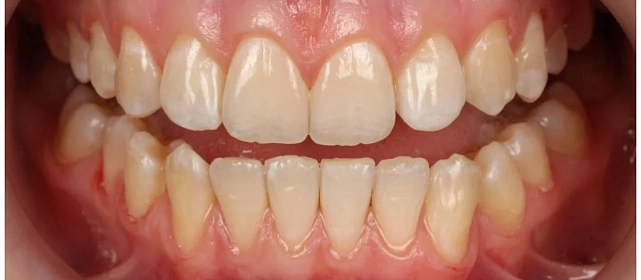

Диагностика

Верхняя челюсть выступала вперёд относительно нижней с обеих сторон (II класс по Энглю). Обе челюсти сужены, зубы стояли скученно. Нарушена кривая смыкания — жевательные зубы были на разной высоте. На двух передних зубах верхней челюсти ранее установлены металлокерамические коронки.

Проблема: Пациентку беспокоили неровные зубы и неправильный прикус. При осмотре нашли сразу несколько проблем: обе челюсти сужены, зубы стоят скученно, верхняя челюсть выступает вперёд (II класс по Энглю), кривая смыкания деформирована — жевательные зубы на разной высоте. На двух передних зубах верхней челюсти стояли старые металлокерамические коронки, которые нужно было учитывать при планировании.